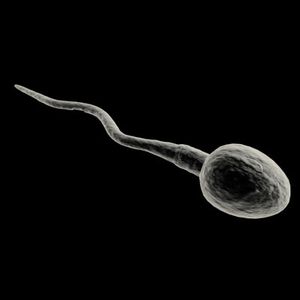

تكوين الحيوانات المنوية

يتم تكوين الحيوانات المنوية في الخصية , وتشتمل عملية تكوين الحيوانات على ثلاثة مراحل متعاقبة هي : التكاثر والنمو والتفلج. كمايتكون من 1)راس السوط و غشاء سيتو بلازم و طحيمن

وظيفة تصنيع النطاف

تستغرق عملية تكوين الحيوان المنوي في الخصية نحو سبعين يوماً. أما مراحل هذا التشكل فهي: تنقسم كل خلية منوية أصلية إلى خليتين واحدة تشكل مثيلة لها، والأخرى تتطور وتنقسم مشكلةً خلايا منوية تمر بمراحل عديدة هي الخلية المنوية الابتدائية primary spermatocyte والثانوية والأخيرة تنقسم انقساماً منصفاً تفقد الخلايا الناتجة عنه نصف صبغياتها ليصير في كل خلية 22 صبغياً جسمياً وصبغياً جنسياً واحداً من نمط X (أنثوي) أو من نمط Y (ذكري) يطلق على هذه الخلايا اسم أرومة النطفة spermatide، وهذه تنقسم انقساماً عادياً لتكون الحيوانات المنوية. وجدير بالذكر أن حصيلة انقسام كل خلية منتشة هو 64 حيواناً منوياً. تتجمع هذه النطاف في الأنابيب المنوية وفي الشبكة الخصوية لتصب في رأس البربخ بوساطة الأنابيب الصادرة عن الخصية. ومن المهم معرفة أن عملية تصنيع النطف لدى الذكر عملية مستمرة منذ البلوغ حتى نهاية العمر ولو أنه يصيبها نوع من التباطؤ بعد سن الستين.